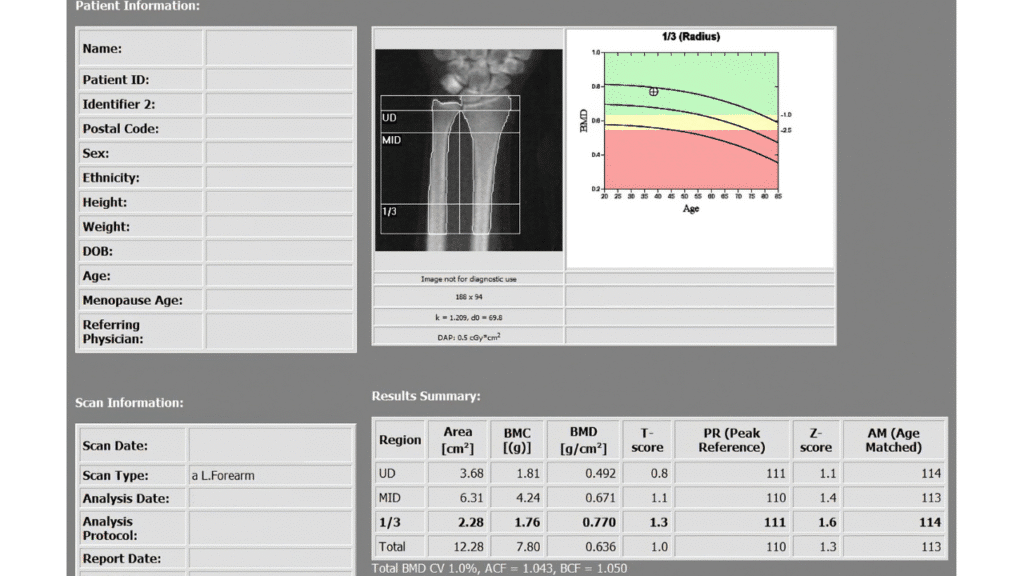

Medical results of a bone scan showing density to help patients learn How PT Helps Prevent Osteoporosis During Menopause in Austin Texas